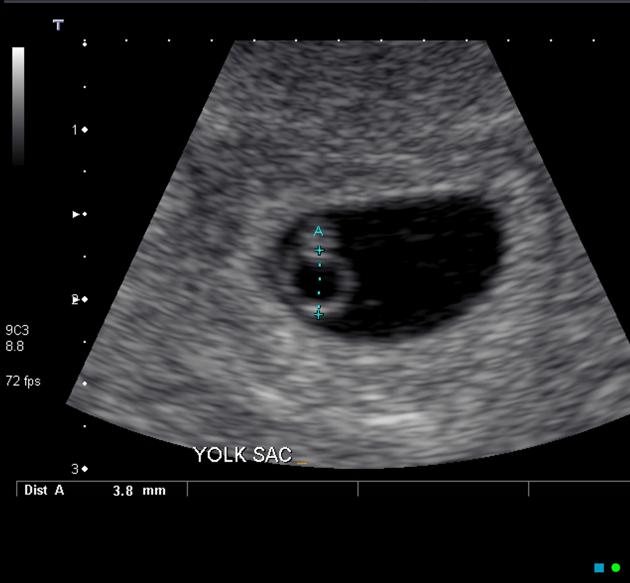

Gebelik kesesi içerisindeki yolk sac kesesi, ultrasonda görülebilecek boyutlara ulaşmamışsa dış gebelik tanısını hızlı bir şekilde koymak mümkün olamamaktadır. Bu durumda iki gün arayla yapılan kanda Bhcg düzeyi testi ile tanı koyabilmekteyiz. İki gün ara ile bakılan BHCG düzeyi; Bhcg değeri 1500 altında ise yüzde 49, 1500-300 arasında yüzde 40, 3000-10000 arasında yüzde 33 artmış olmalı. Fakat dış gebelik tanısı koyabilmek için kan testleri ultrasonografi bulguları ile birlikte değerlendirilmelidir.

Yolk sac kesesi gebelik kesesi içerisinde görülüyorsa ve gebelik kesesi rahim dışındaysa, kan testine gerek olmadan dış gebelik tanısı koyabilmekteyiz.